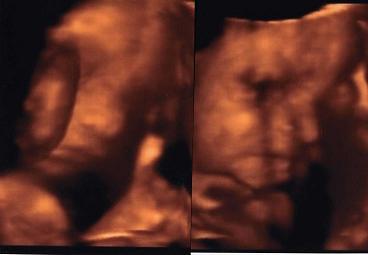

Pihenj azért néha egy kicsit, bár ha jól emlékszem nekem is volt olyan időszakom a terhesség alatt, amikor úgy éreztem kétszer annyi energiám van, mint eredetileg és nagyon pörögtem. Élveztem ahogy a Máté rugdosódik bent a pocakomban és követeli a helyzetváltoztatást, mert nem fért el.